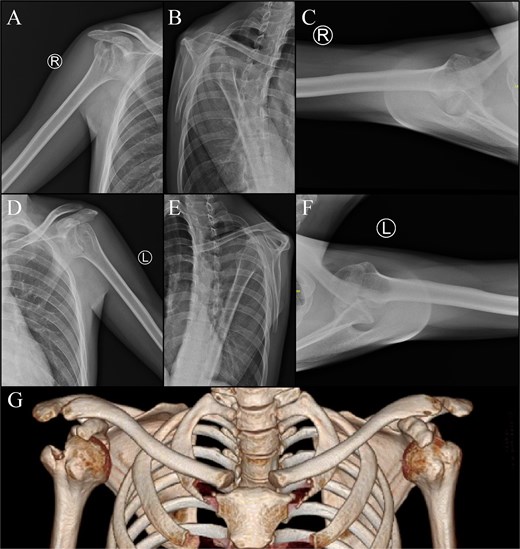

The patient was positioned in a beach-chair position. After identification of the biceps and pectoralis major tendon, tenotomy, and tenodesis were performed, respectively. Fibrotic tissues and adhesions found in subcoracoid and subacromial area were then released. The GT, along with supraspinatus and infraspinatus tendons were identified, then GT osteotomy was done in a straight-line manner (Fig. 3). Posterior capsulotomy was performed for better visualization. The Hill-Sachs lesion and glenoid were exposed by lifting and internally rotating the arm, allowing removal of adhesions. After preparation of the glenohumeral joint, the humeral head was reduced using a Hohmann retractor. The GT was initially secured with temporary K-wires which was then confirmed with fluoroscopy before performing definitive fixation using a PHILOS plate [8]. Illustration of the technique is described in Fig. 4. If intraoperative assessment reveals a shortened or tightened subscapularis muscle, the K-wire can be retained for up to 3 weeks postoperatively to maintain adequate stabilization, as done in the left shouldercase.

The patient was satisfied with the outcome, with normal activity regained 3 months after surgery. During the 1-year follow up of the right shoulder (Fig. 5), full ROM was achieved for flexion, extension, abduction, internal rotation, and external rotation (Table 1). Improvements of pain and functional score after 1 year was noticed with 0 visual analogue scale score, 100 The American Shoulder and Elbow Surgeons score and 0.8 disabilities of the arm, shoulder, and hand score. By the ninth month following the left shoulder surgery, improved ROM was noticed. Post-operative radiographic assessment of the right and left shoulders was conducted, as shown in Fig. 6.

Post-operative radiographs: (A) right shoulder; (B) left shoulder.